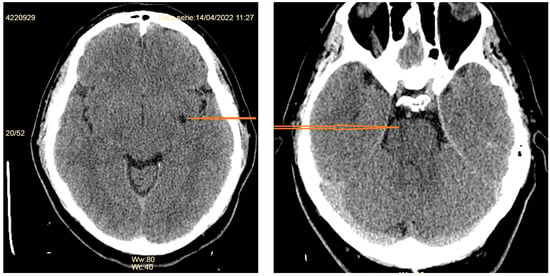

- Subdural fluid collections—mostly bilateral hygromas—are described in 43–50% of patients [5,19]. Hygromas occur because of the enlargement of the subdural space secondary to the loss of the CSF, while subdural hematomas may be caused by tearing of the abnormally engorged and dilated cortical veins [32]. Drainage of these collections will not resolve them successfully if the CSF leak is not identified and treated [36].

- Signs of brain sagging include flattening of the ventral pons, effacement of the prepontine and perichiasmatic cisterns, or downward displacement of the cerebellar tonsils and brain stem [5,8], which may mimic Chiari type 1 malformation. However, in SIH, the tonsils maintain normal shape and do not descend more than 5 mm below the foramen magnum [37]. Moreover, the findings associated with syringomyelia would argue for the diagnosis of Chiari type 1 malformation [32].